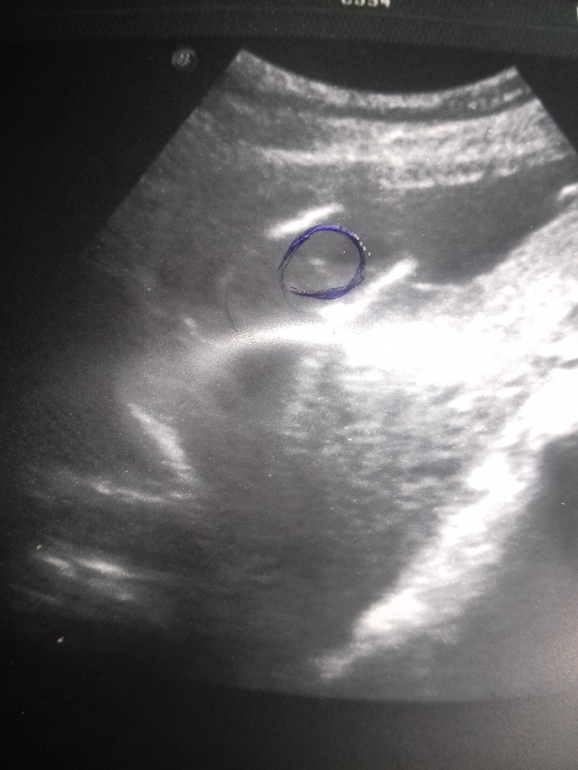

Девочки,привет)Помогите разобраться.Вторая беременность,16 недель.На платном узи сказали,что девочка.Но нужно еще в 20 недель сделать для точности.Узистка даже не развернула монитор,ничего не показала,просто,жуя жвачку,поковырялась полчаса и сделала заключение и фото.Я так расстроилась,т.к. хотелось конкретики.Могла ли она ошибиться?Просто первой дочей мне пол сказали через секунд 30 и дали гарантию 100%.Я даже не сомневалась и не морочила голову...А здесь все вызывает сомнение...Да и сама специалистка с жвачкой на приеме и молчанием все узи,даже не показав мне ребеночка...Учитывая,что обращалась в платную...Фото узи у меня в дневнике...